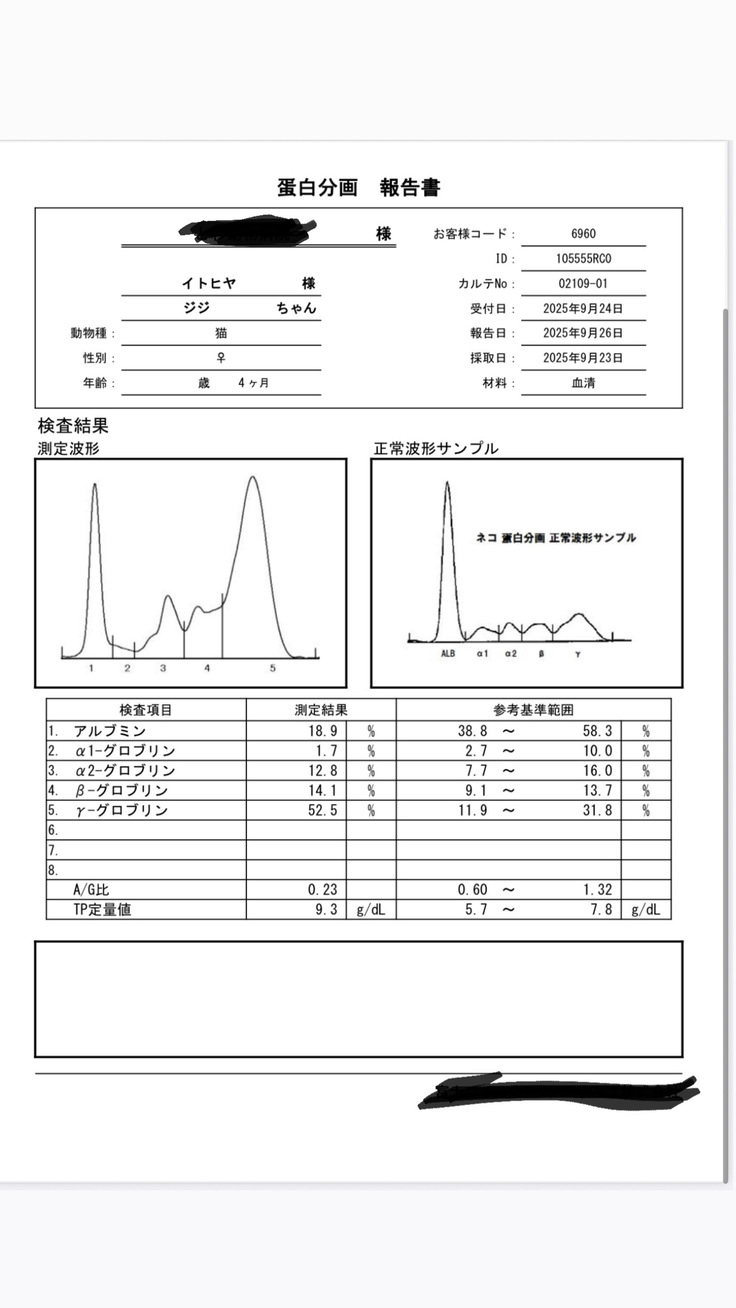

すぐに血液検査など詳しい検査をしていただき、出た結果です。

タンパク質からの計算式に基づいて、この時点でおそらくFIPで間違いないだろうとの診断でした。

そして詳細の検査の結果、9/26、正式にFIP(Wetタイプ)と診断を受けました。